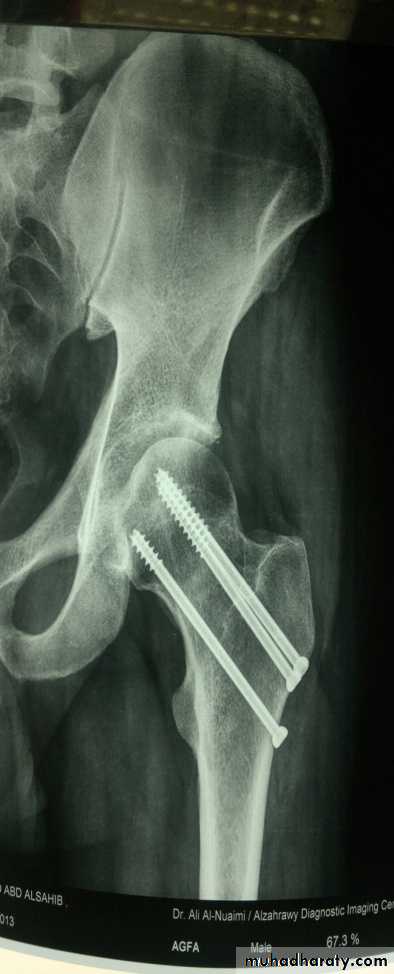

A- intracapsular fracture neck of the femur :

Mechanism of injury :This fracture usually result from a fall directly on to the greater trochanter . In very osteoporotic patient less forced is required . Sometimes no more than catching a toe in the carpet and twisting the hip into external rotation .

Classification : the most useful classification for intracapsular fracture neck of femur is that of (Garden classification) which based on the degree of displacement .

Stage one : is incomplete impacted fracture .

Stage two : is complete undisplaced fracture .

Stage three : complete fracture with moderate displacement .

Stage four : is severely displaced fracture .

this fracture is complicated by two main problems which are :

1- ischemia of the head of the femur .2- tardy union .

Treatment :

The first measure is to apply skin traction to splint the fracture and to control the pain , and give analgesic for pain relieve .

Operative treatment is always mandatory .

Displaced fracture will not unite without internal fixation .

Old people should be got up and active without delay to avoid pulmonary complication and bed sore .

The operation should be done as early as possible to avoid risk of complications .

The principle is perfect reduction , secure rigid fixation and early mobilization .

the fixation should be done by internal fixators like compression screws , plate and screws , dynamic hip screw ……etc .

In patient above 65 years with displaced fracture , partial hip replacement or total hip replacement.